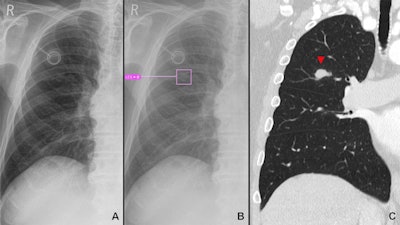

AI-Rad detects five specific radiographic findings: pulmonary lesions, consolidation, atelectasis, pneumothorax, and pleural effusion. It received the CE mark for use in Europe in 2020. The algorithm generates a confidence score on a scale of 1 (low) to 10 (high) for each finding, which expresses its certainty for the presence of that particular finding; only scores of 6 or more are displayed.

AI-Rad achieved a higher sensitivity for the detection of lung lesions compared with the radiologist readers (83% vs. 52%), consolidations (88% vs. 78%) and atelectasis (54% vs. 43%) compared with the radiologist reports. The sensitivity of the AI-Rad for the detection of pleural effusions was lower compared with the reports, however, at 74% versus 88%.